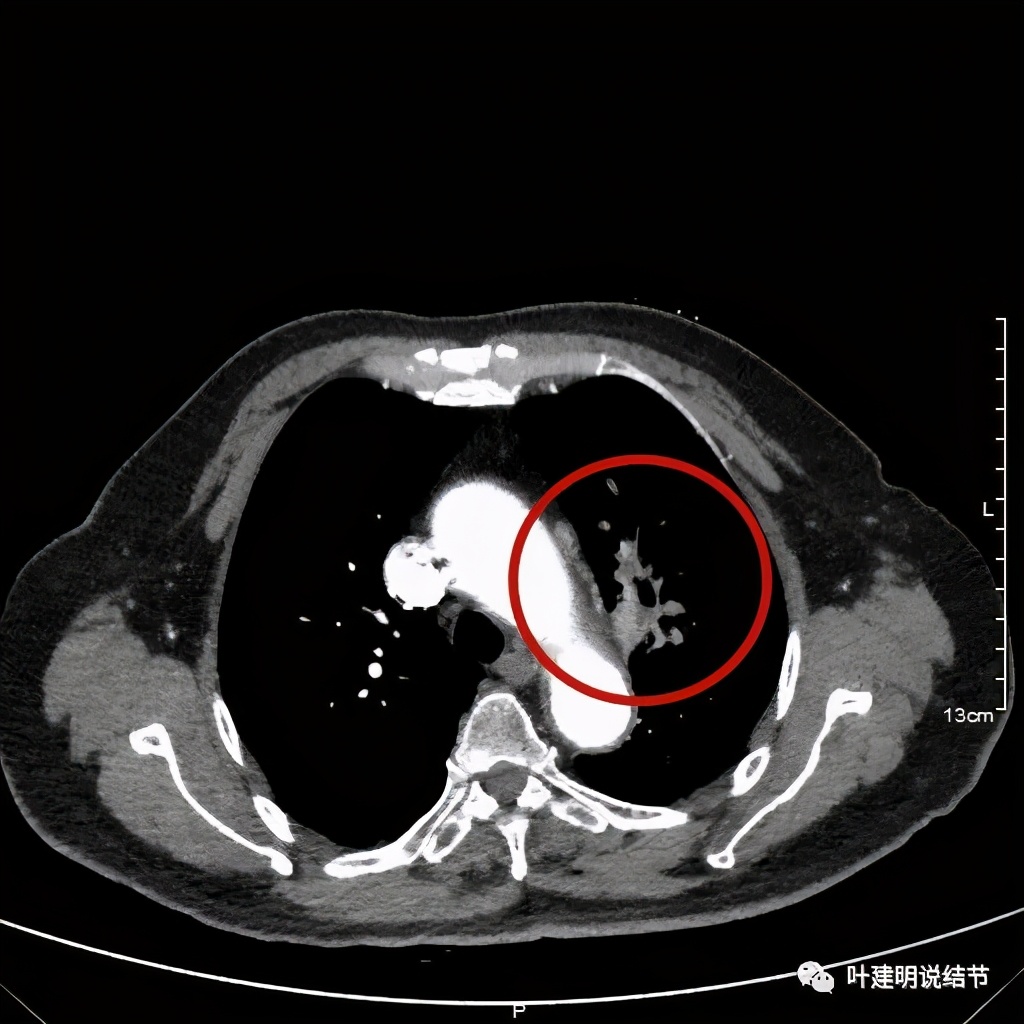

肺窗见原左上叶巨大占位已经明显缩小,甚至几乎不见了!而且上图示左上叶支气管清晰可见,内壁变光滑。纵隔窗增强又是如何的呢?

左上肺基本已经不见肿瘤,只在主动脉旁少许软组织影